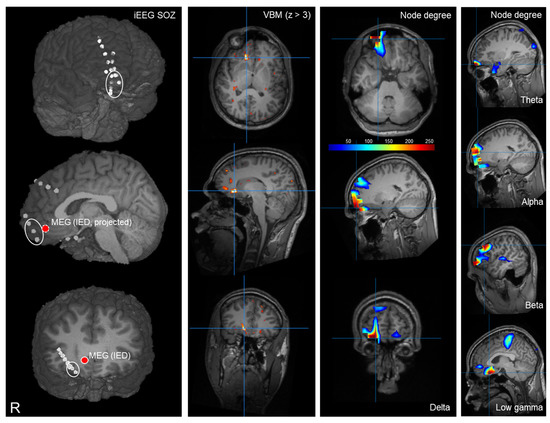

Figure 1.

Example case of a patient with right fronto-polar focal cortical dysplasia type IIb. The first column shows the iEEG findings; fronto-polar SOZ electrodes are circled. Lower inset shows depth electrodes inserted into the lesion. The circle marker shows the localization from routine MEG analysis based on IEDs. Second column shows MRI postprocessing (voxel-based morphometry, MAP19, combined z-score, thresholded at z > 3) superimposed on the patient’s T1. Third column shows delta band node degree (thresholded at 95th percentile to illustrate maximum, see Supplementary Figure S1 for full distributions). Right-most column shows sagittal slices of node degree in the other frequency bands (thresholded). The patient underwent epilepsy surgery and was seizure-free thereafter for several years; however, the patient then developed recurrent seizures with a reduced frequency.